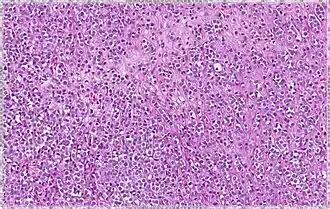

| Solid | 10% | Sheets of classical-appearing cells with little intervening stroma | |

| Alveolar | 5% | Aggregates of classical-appearing cells | |

| Pleomorphic | Classical-appearing but with pleomorphic cells. It may include signet-ring cells, or plasmacytoid cells (pictured) which have abundant cytoplasm and eccentric nuclei. | ![]() |

Histopathology of invasive lobular carcinoma (ILC), next to lobular carcinoma in situ (LCIS) -

Invasive lobular carcinoma demonstrating a predominantly lobular growth pattern -

Lobular breast cancer. Single file cells and cell nests. -

ILC may be subtle on low magnification (left). Higher magnification (right) shows invasive growth pattern and vesicular nuclei with prominent nucleoli.